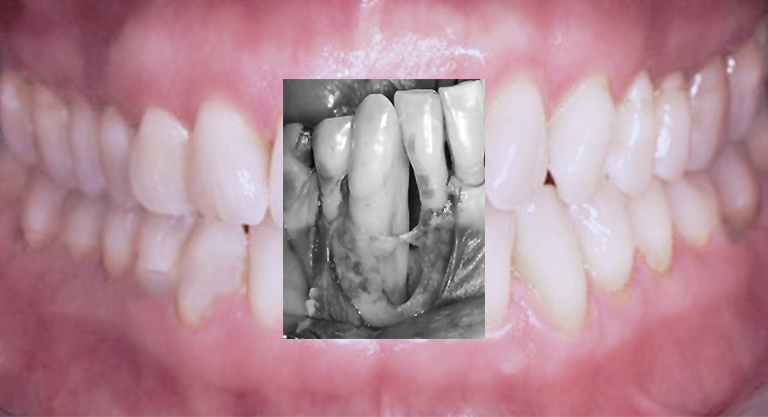

Diagnostik von Zahnfleisch-Knochenerkrankung

Nichtchirurgische und unterstützende Therapie

Chirurgische, regenerative Interventionen